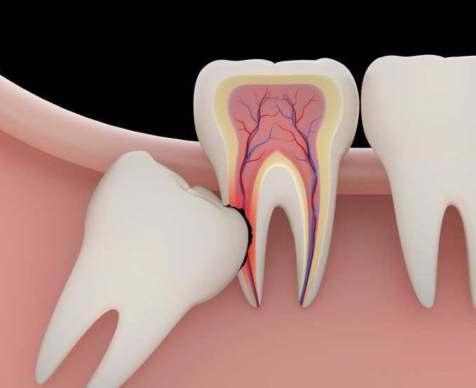

• Cirugía terceros molares